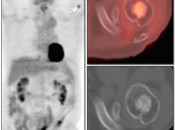

Assessing Response to Therapy & Prognosis:

- Early Response: Non-responders can be offered alternative therapy.

- Late Response: Assess success or failure of therapy, and ultimate outcome.